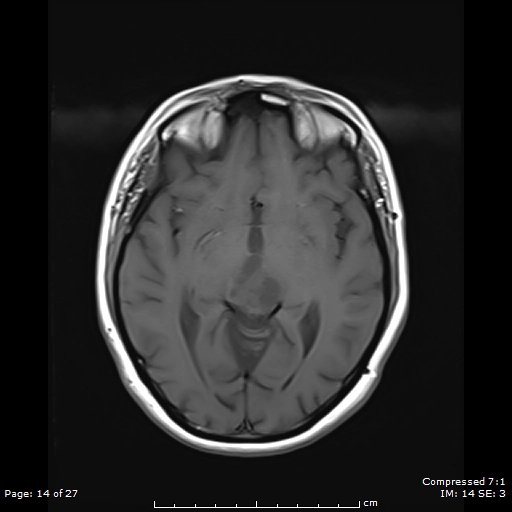

U lympho hệ thần kinh trung ương (Central Nervous System Lymphoma - CNS Lymphoma)

U lympho hệ thần kinh trung ương liên quan đến suy giảm miễn dịch (Immunodeficiency-associated CNS lymphomas)